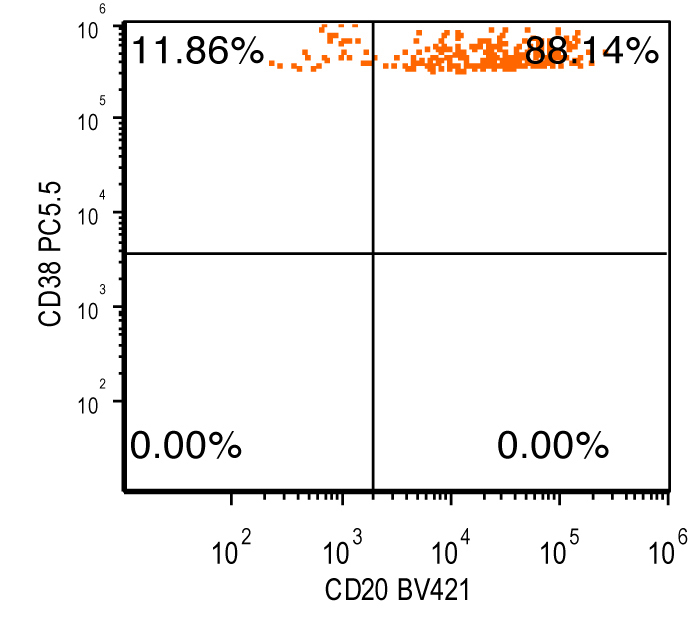

- Flow cytometry: monoclonal B cells with typical immunophenotype and monoclonal plasma cells

- Immunophenotype of LPL cells: IgM+, CD19+, CD20+, CD22+, CD25+, CD10-, CD23-, CD103-, variable CD138

- Immunophenotype

- Positive: IgM, CD19, CD20, CD22, CD79a, CD25 and CD38 frequent expression

- Negative: CD5, CD10, CD103, CD23; however, CD23 expression is not uncommon in some cases

Flow cytometry description

Flow cytometry images

Contributed by Ling Zhang, M.D. and Caroline An, M.D.